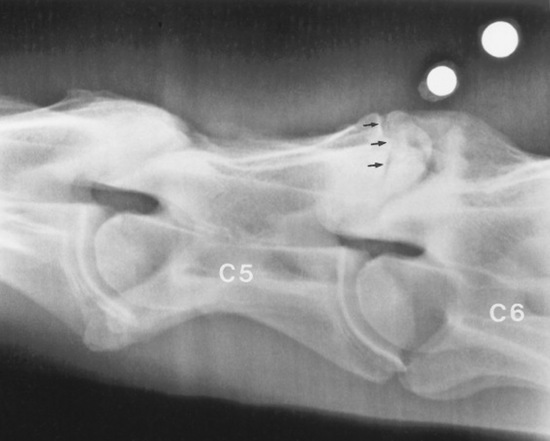

A complete myelographic examination should include neutral and stressed (flexed and extended) views of the cervical vertebrae.1863,1883 Horses with dynamic spinal cord compression show obliteration of the dorsal and ventral contrast columns during ventroflexion of the neck (Fig. 35-29), whereas spinal cord compression is not apparent with the neck in the neutral position. Static vertebral canal stenosis is characterized by constant spinal cord compression regardless of cervical position (Fig. 35-30). In some cases of static compression, ventroflexion of the neck stretches the ligamentum flavum and relieves spinal cord compression, whereas hyperextension exacerbates compression. In horses with obvious sites of spinal cord compression on neutral myelographic views, excessive flexion and extension of the neck should be avoided while obtaining dynamic views to prevent exacerbation of spinal cord injury.

Fig. 35-30 Myelographic examination of C5 through C7 with the cervical spine in neutral position. Static spinal cord compression is demonstrated by obliteration or narrowing (to less than 2 mm) of the dorsal and ventral contrast columns at C5-C6 and C6-C7 (arrows).